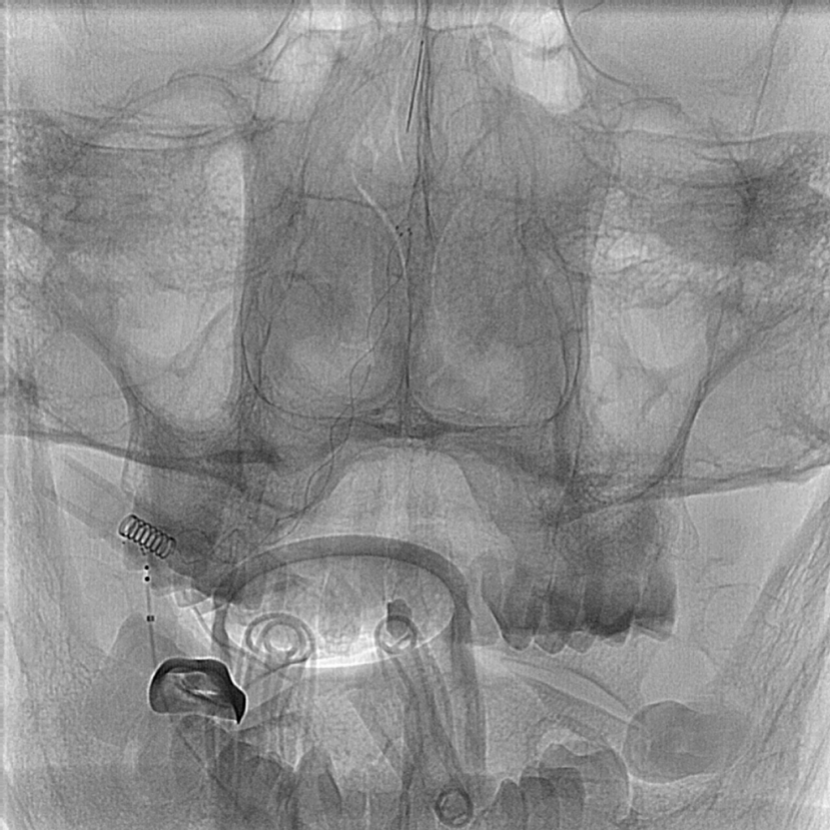

扩张后造影提示LVA明显改善,基地动脉中段狭窄50%,考虑病变节段过长,置入多枚支架增加术后支架内再狭窄或闭塞风险,故决定于椎动脉V4段置入支架成型。病变长度约40 mm,Neuroform Winspan均无合适型号 Enterprise 37 mm支架手头无货,拟用LVIS 4.5 mmX30 mm支架行支架成型术。

支架置入术后蒙片及正侧斜位造影,见支架上端位于AICA水平以上,支架脚跨过AICA开口,锁骨下动脉造影显示RVA前向血流明显改善,双侧AICA显影